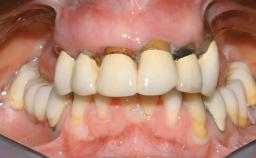

Immediate Loading of Six Implants in the Maxilla and Final Restoration with a Full-Arch CAD/CAM Zirconia FDP

Prosthesis Type FDP

Defining Characteristics Fully edentulous upper jaw to be rehabilitated with an implant-borne fixed dental prosthesis